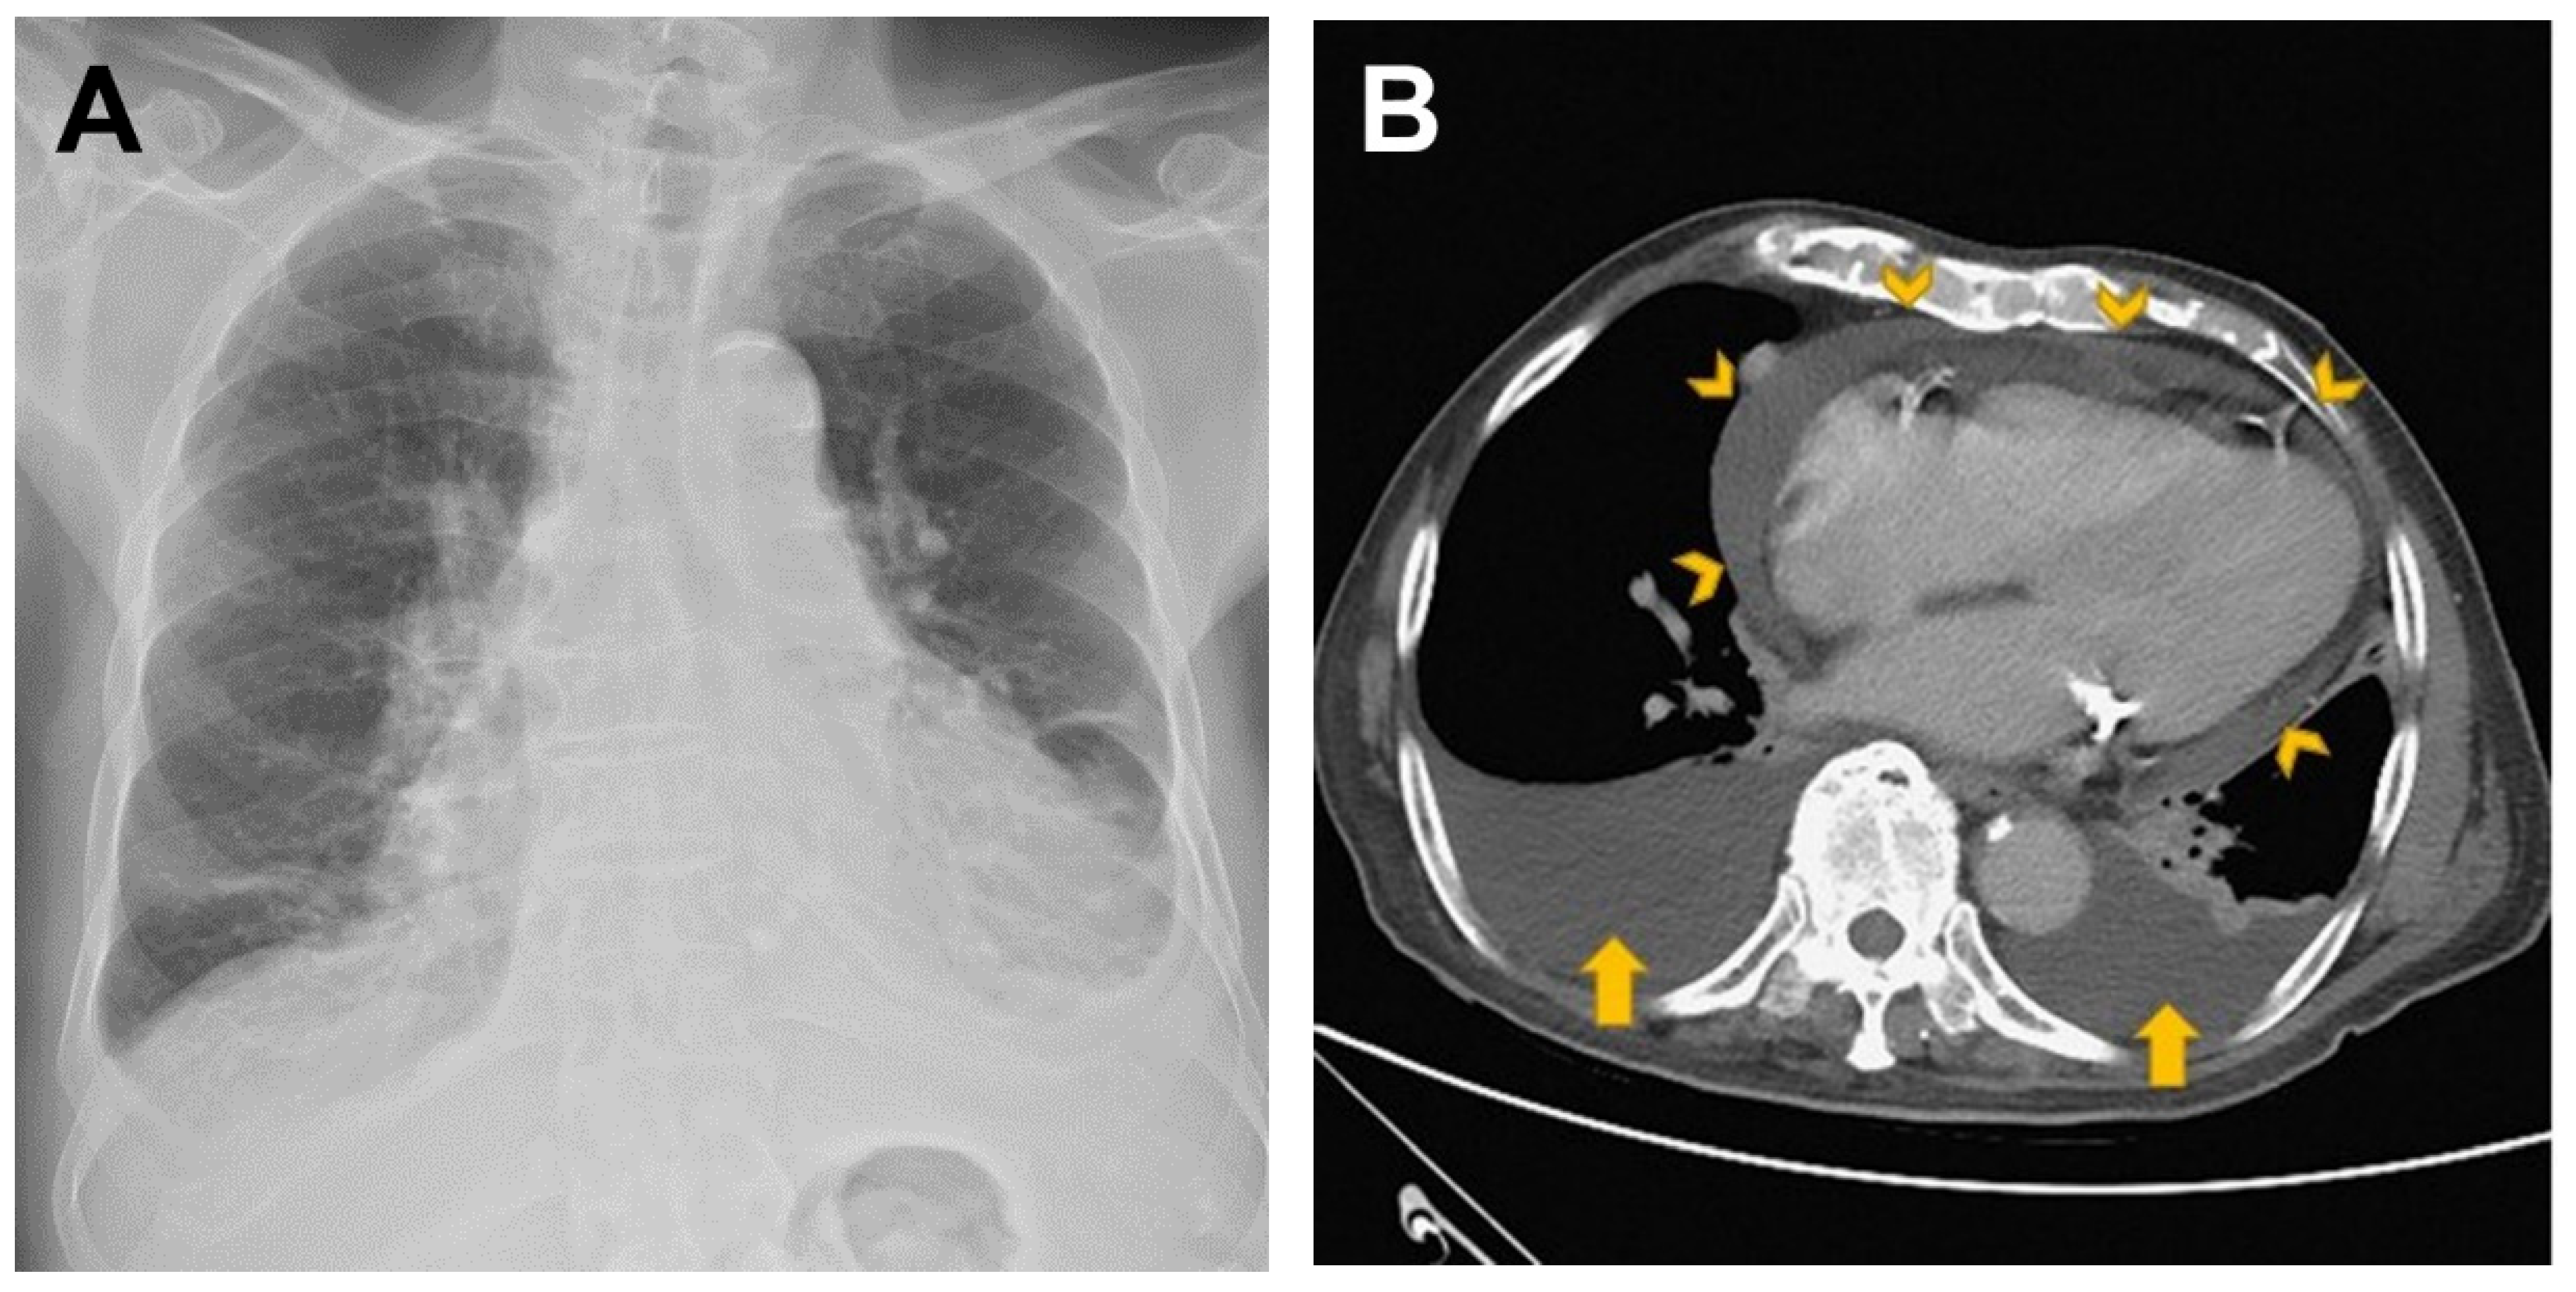

2. Case Presentation